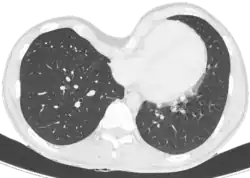

Le diagnostic est clinique, par l'examen de la déformation thoracique. On peut toutefois proposer la réalisation d'une tomodensitométrie thoracique, permettant le calcul de l'index de Haller, évaluant de manière objective la sévérité de la déformation et permettant de rechercher une compression cardiaque, trachéale ou œsophagienne. Des explorations fonctionnelles respiratoires évaluent l'impact de la déformation sur la fonction pulmonaire, et une épreuve d'effort recherche l'impact sur les capacités d'effort.